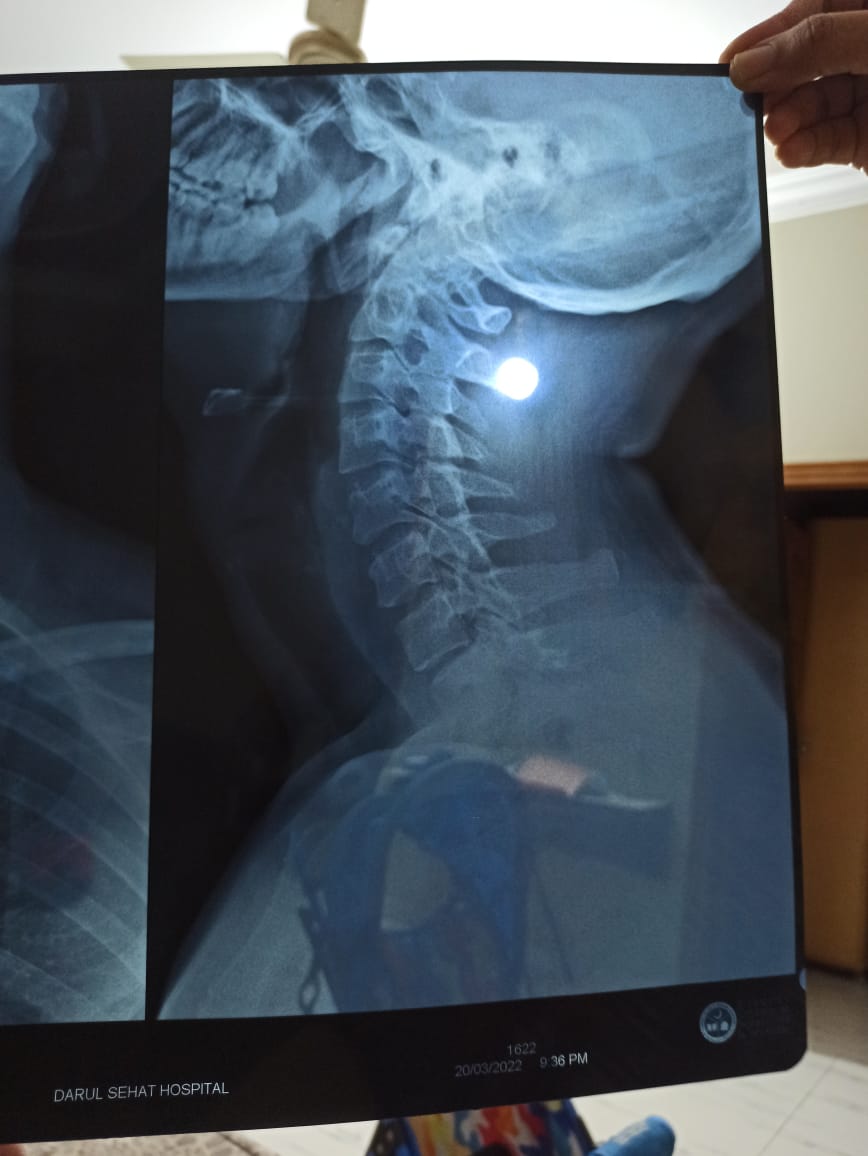

I have been stiff neck problems for quite sometime now where I wake up with a stiff neck which leads to headaches. I work in IT and have a desk job 9 hours a day. I have recently had my neck X-ray done on the advice of my doctor. I seek help as I will not be able to visit my doctor due to work. Doc works in the weekdays and so do I. I need someone qualified to take a look at my x-ray and tell me if there is anything wrong. I would be grateful. Bless you!

Attach Photo here: